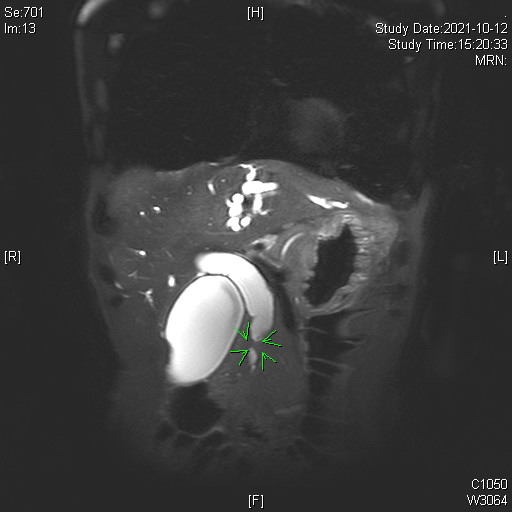

1. Multiphase CT and MRI

- High-resolution contrast-enhanced CT and MRI scans are first-line tools for evaluating biliary masses, ductal obstruction, vascular involvement, and metastatic spread.

- MRI with MRCP (Magnetic Resonance Cholangiopancreatography) is particularly useful for visualizing the biliary tree non-invasively and assessing the level and extent of bile duct strictures or masses.